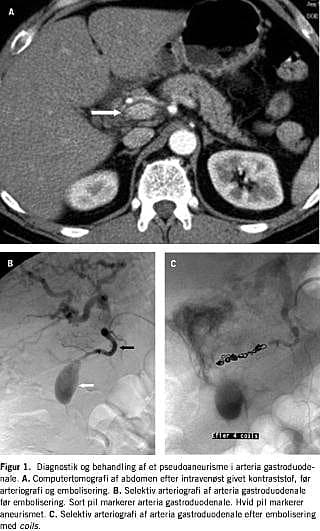

Patienten var en mand født i 1950 og siden april 2001 kendt med alkoholinduceret kronisk pankreatitis. Patientens pan-kreatitis blev kompliceret af dannelse af en pseudocyste ved pancreas, som blev tømt ultralydvejledt tre gange i 2001. Primo januar 2002 havde patienten en et døgn varende episode med melæna og blodtransfusionsbehov. En gastroduodenoskopi viste gastritis og duodenitis, og patienten blev sat i behandling med en protonpumpehæmmer. To uger senere fik han pludselig stærke smerter i den øvre del af abdomen med udstråling til ryggen og op i brystet. Smerterne var væsentligt værre end hans sædvanlige smerter. Ved en objektiv undersøgelse var patienten udtalt øm i epigastriet. Biokemiske undersøgelser viste normale forhold, bortset fra en marginal forhøjet S-amylase og c-reaktiv protein. En computertomografi (CT) viste et pseudoaneurisme i arteria gastroduodenale. Pseudoaneurismet var beliggende i en pancreaspseudocyste (Figur 1A ). Der blev foretaget arteriografi, som viste et 2×3 cm stort pseudoaneurisme i arteria gastroduodenale (Figur 1B). Herefter blev der foretaget superselektiv arteriografi af arteria gastroduodenale, og arterien blev endovaskulært emboliseret med coils både proksimalt og distalt for pseudoaneurismet (Figur 1C). Patientens smerter aftog betydeligt efter emboliseringen, og han blev udskrevet tre dage senere. En kontrol-CT efter en måned viste ingen tegn på recidiv af pseudoaneurismet. Patienten var velbefindende 26 måneder efter behandlingen.